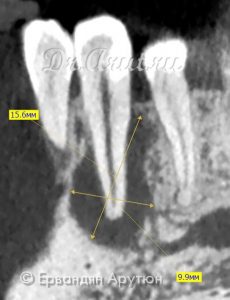

Объективно: Подвижность зубов 32 и 33 I степени. Свищ на вестибулярной поверхности между 33 и 34 зубами. Перкуссия 33 зуба безболезненная, термометрия безболезненная. На вестибулярно-дистальной поверхности пломба. ЭОД выше 200 μА. 32 интактный. ЭОД 6 μА. Термометрия болезненная, боль проходит сразу, перкуссия безболезненная. На компьютерной томограмме очаг просветления в области 33 и 32 зубов (периапикальный абсцесс) размером 16×16×6 мм. В анамнезе отсутствовали жалобы на боль в 33 зубе. После трепанации 33 зуба и инструментальной обработки корневого канала произошло обильного выделение гноя.

Через 3 месяца (апрель 2018) пациент также не предъявлял жалоб. Была произведена инструментальная и медикаментозная обработка корневого канала (3% гипохлоритом натрия и 3% перекисью водорода). Канал запломбирован AH plus с гуттаперчевым штифтом методом вертикальной конденсации. На момент пломбирования оставался небольшой очаг просветления в области верхушки корня 33 зуба. Остальная часть костной ткани восстановилась, в том числе и периодонт.